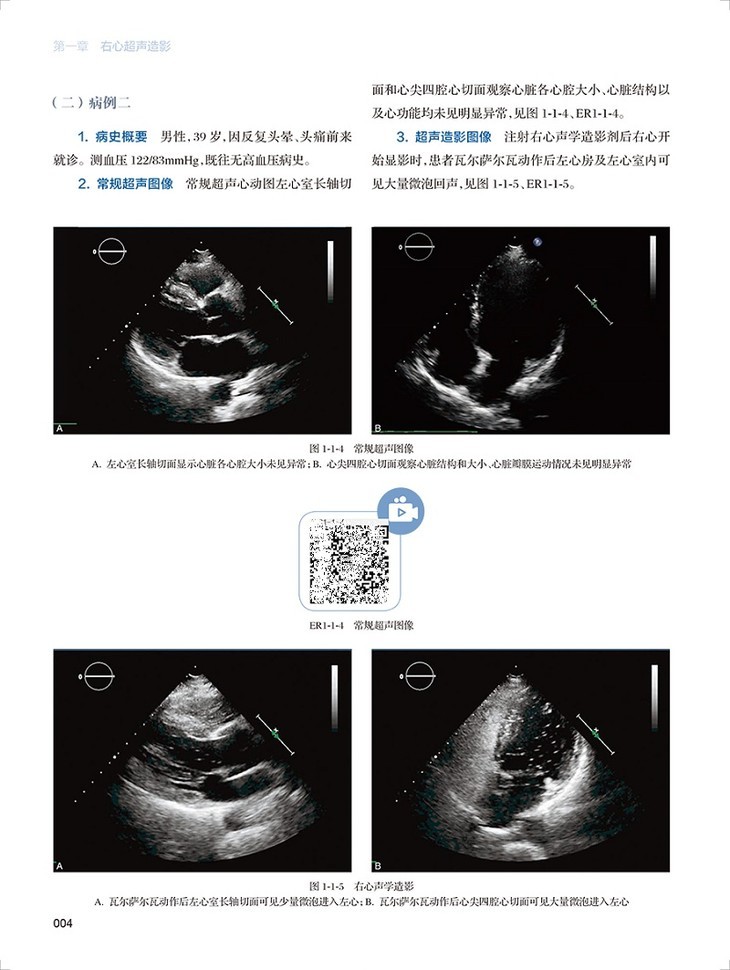

心血管超声造影图鉴共有文字内容60千字,图片454幅,视频212个。全书分为三章三十一节内容,分为左心超声造影、右心超声造影和血管造影三个板块,包括了卵圆孔未闭右向左分流、肺动静脉瘘、永存左上腔静脉、房间隔缺损封堵术后评估右向左的残余分流、部分型肺静脉异位引流、应激性心肌病、左心房黏液瘤、心腔内血栓等疾病的超声造影表现。每个病例分为病史概要、常规超声图像、超声造影图像、经食道超声心动图和超声造影要点五个小标题,内容精炼、脉络清晰、一目了然。各个病例配了多张彩图和视频进行对照,读者可以扫描图片右侧二维码观看视频,方便快捷。